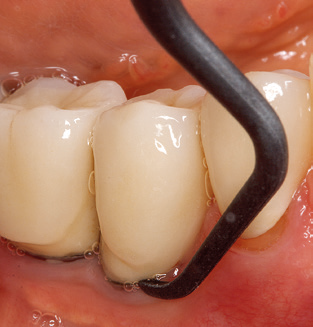

Unerlässlich für die UPT implantat­ prothetisch versorgter Patienten sind natürlich Arbeitsspitzen für die Reini­gung von Implantatoberflächen. Der Implantatreinigungsaufsatz des hier verwendeten Systems zeichnet sich dabei durch eine spitz zulaufende sechskantige konische Form aus. Dieses Design erlaubt ein leichtes atraumatisches Eindringen in die periimplantäre Tasche und zeigt eine gute Reinigungsleistung (Abb. 7).

Abb. 4: Für das Sondieren an dentalen Implantaten sind biegsame, millimeterskalierte Sonden empfehlenswert (z.B. Colorvue Kit PCV11KIT6, Hu-Friedy). – Abb. 5a und b: Eine gerade Arbeitsspitze (1P, W&H Dentalwerk Bürmoos GmbH) ist universell für die Instrumentierung natürlicher Zähne geeignet. – Abb. 6: Für die Bearbeitung schwer zugänglicher Bereiche der Zahn- und Wurzeloberflächen (z.B. Furkationen) bieten sich gebogene Arbeitsspitzen (3Pr/3Pl, W&H Dentalwerk Bürmoos GmbH) an. – Abb. 7: Die spitz zulaufende sechseckige Implantatreinigungsspitze (1I, W&H Dentalwerk Bürmoos GmbH) ermöglicht eine atraumatische und effiziente Reinigung der Kronen- und Abutmentoberflächen. – Abb. 8: Für die manuelle Instrumentierung der Implantatoberflächen sind Titan- oder Carbonküretten geeignet.